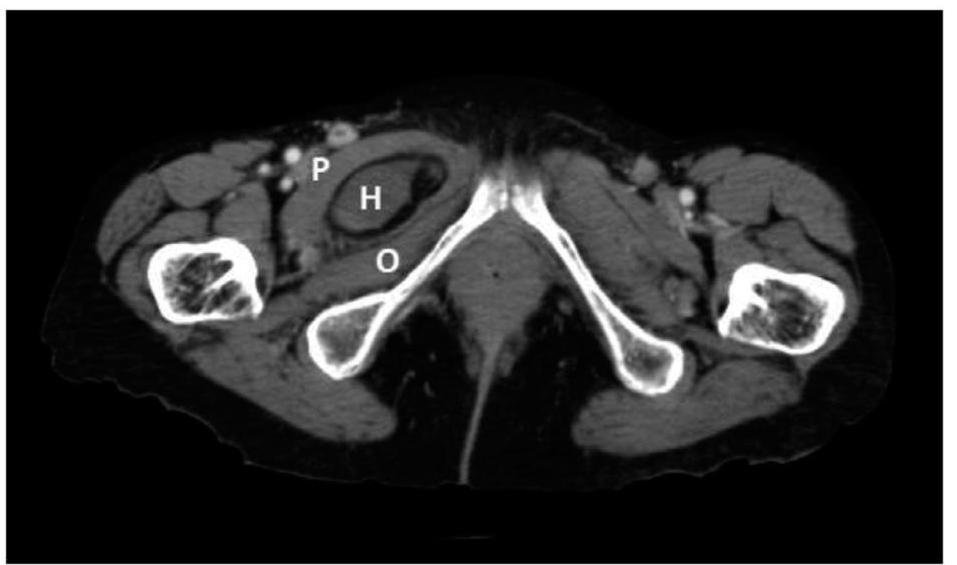

# OTRAS HERNIAS ## HERNIA DE LITTRE En el interior del saco herniario se encuentra un **DIVERTÍCULO DE MECKEL**.  ## HERNIA DE RICHTER Herniación de una **PORCIÓN DE LA PARED ANTIMESENTÉRICA** del intestino delgado. ## Richter's Hernia  # HERNIA DE SPIEGEL En el punto de unión del borde lateral del recto abdominal con la línea semilunar de Douglas. Surgen laterales e infraumbilicales.  Hernia de Spiegel vista anatómica.  ## HERNIA DE AMYAND Contiene una **APENDICITIS AGUDA**. ## HERNIA OBTURATRIZ Salen por el orificio obturador o infrapúbico. - Generalmente en **mujeres mayores**. - Rara vez son palpables. - Producen dolor que se extiende medialmente al **muslo** y cuadros obstructivos. - Diagnóstico por **TAC**.